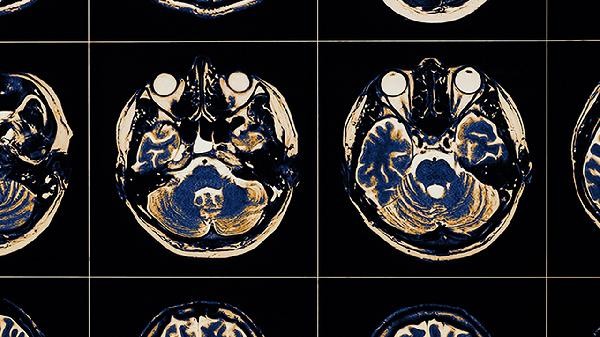

The formation of brain memory involves three core processes: information encoding, storage, and retrieval, mainly related to the synergistic effects of brain regions such as the hippocampus and prefrontal cortex. Memory can be divided into sensory memory, short-term memory, and long-term memory, and its neural basis includes mechanisms such as synaptic plasticity and long-term potentiation.